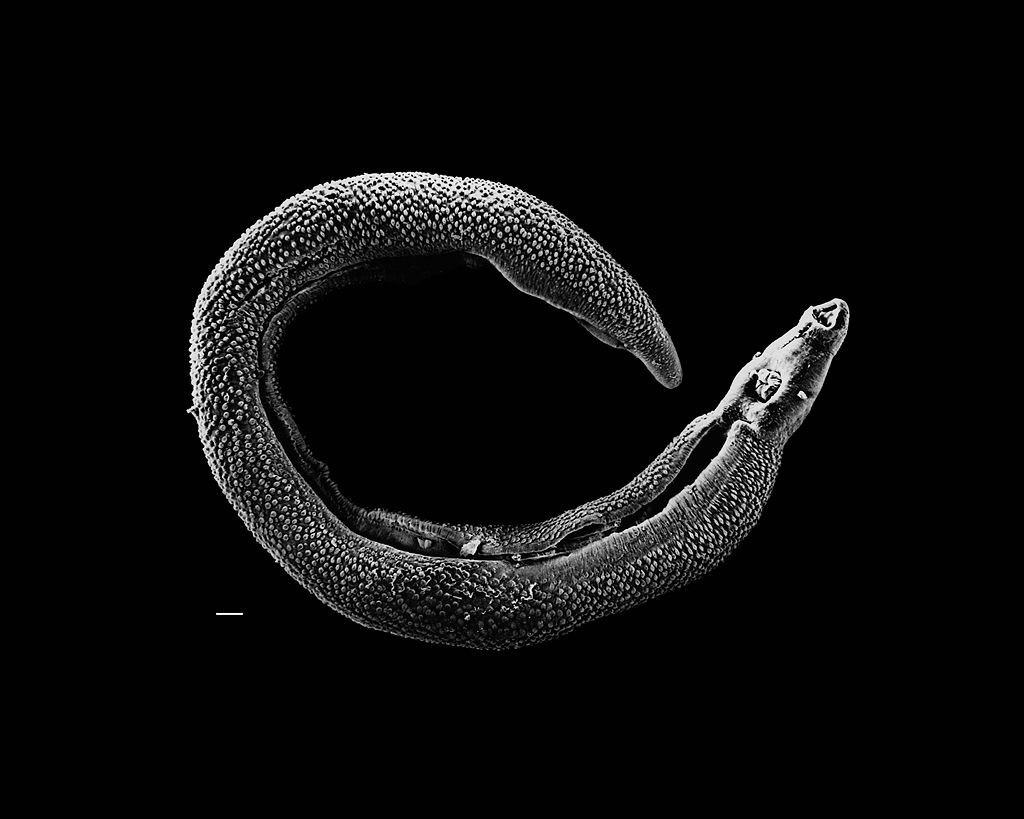

图注:电子显微镜下合抱的血吸虫

血吸虫是一种寄生蠕虫,但是它们却是雌雄异株的蠕虫,而且雌雄之间表现出强烈的两性二态性,雄性比雌性大出许多,这在“蠕虫界”是非常罕见的(大部分寄生蠕虫都是雌雄同体)。

它们虽然是雌雄异株,但是雌雄是结合在一起生存的,雄虫将雌虫包围在自己的虫管中,一直到雌虫成年,这是它们“裂体吸虫”名字的由来。

其实,雄性血吸虫和雌性血吸虫有点像“童养媳”的关系,雄性负责吸食宿主,它会把自己吸食的一部分营养转移到雌性体内,甚至是一些类似人类生长发育的激素都是由雄性提供——当雌雄合抱一起之后,雄性会帮助雌性完成发育。